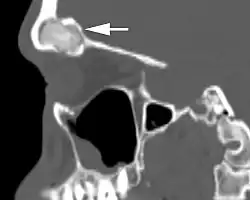

Imaging findings

When performing imaging studies, bone windows in computed tomography studies are the best. The lesion is usually identified as a well demarcated, expansile mass with an ossified rim at the periphery. Calcifications are noted throughout. MRI shows a variable finding depending on T1 or T2 weighted images, dependent on the amount of bone to fibrous connective tissue ratio.[2]